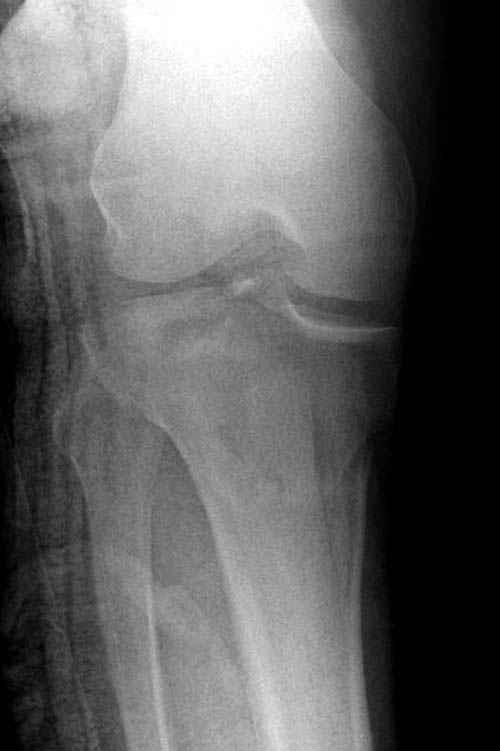

На представленных предоперационных срезах КТ огромный задне-медиальный фрагмент расположен больше кзади, чем медиально. Для планирования, кроме поперечных срезов, надо ориентироваться на корональные срезы, которые укажут топографию верхушки медиального фрагмента.

При сложных переломах тибиал плато для своего рода Damage Control мы иногда применяем поэтапную тактику. Сперва оперируется одна сторона, а потом после рекондиции мягких тканей окончательный этап.

Доступ к медиальной стороне задний или медиальный, через pes или в пространстве между medial gastroc мышцы.

Надеюсь, представленные снимки разных случаев помогут разобраться в тактике, и критика примется без личной обиды.